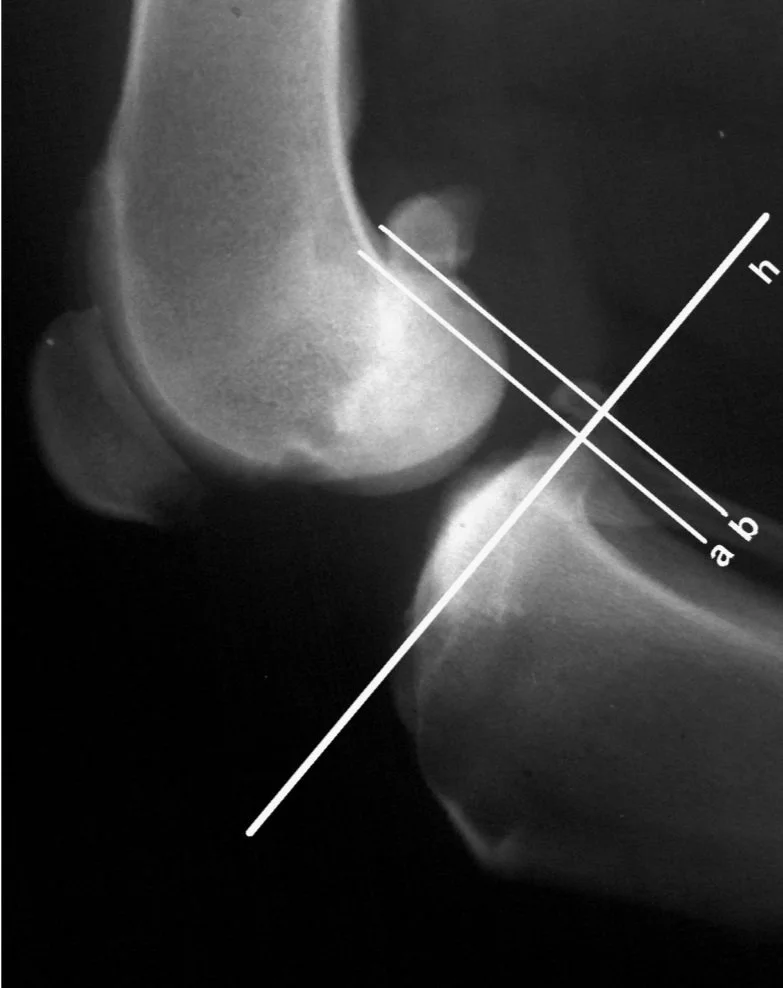

If your brain is a little more scientific-based and needs a more precise assessment, that yes, the tibia is cranially subluxated, there is a measurement you can do. Zatloukal et al (2000) created a more precise measurement of subluxation. First, a line (h) is placed parallel to the tibial plateau. Secondly, two lines are then placed perpendicular to this line, The first line (b) runs caudal to the caudal aspect of the lateral femoral condyle and the second line (a) caudal to the caudal aspect of the caudal tibial condyle.

Image above shows the same stifle subluxated by specific 90/90 stress positioning. Note the smaller space between parallel lines due to cranial displacement of the tibial.